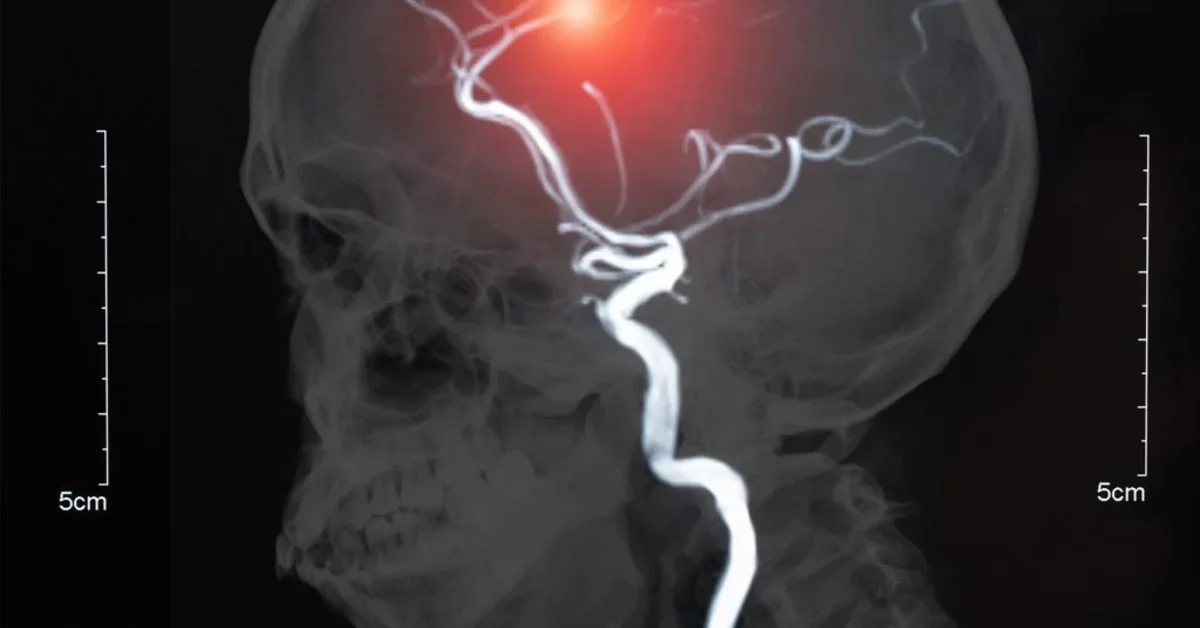

Intracranial aneurysms (ICAs) are an increasingly common finding, both from incidental discovery on imaging studies and on autopsy; it is estimated that anywhere from 1-6% of the American population will develop this problem. Unfortunately, while our ability to detect ICAs has grown, our fundamental understanding of this disease entity remains lacking and significant debate continues in regards to its treatment. Given the high degree of mortality and comorbidity associated with ruptured intracranial aneurysms, it is imperative that new insights and approaches be developed to inform medical decision making involving ICAs.